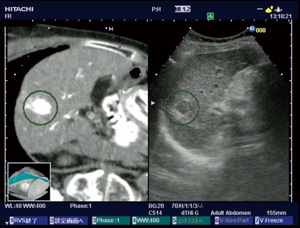

1.Real-time Virtual Sonography(RVS)

CT,MRから,観察中の超音波画面に対応するMPR像をリアルタイムに同時表示する世界初の機能である(図6)。この技術は,超音波ガイド下の治療支援,超音波検査の教育支援などで使用され,高い評価を得ている。

さらに,USボリュームデータと,観察中の US画像との同時表示が可能となった(図7)。USボリュームデータの取得時に,磁気センサを使用するので,位置合わせの手間がなく容易に使用でき,治療直前のUSボリュームデータでのMPR像を治療時や治療後に参照可能である。 |

図6 RVS |

図7 肝がん治療後のRVS

岡山大学消化器内科小林功幸先生・中村進一郎先生 ご提供 |